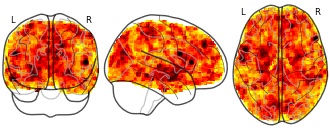

License information was derived automaticallyDescriptionResting-state functional magnetic resonance imaging (RS-fMRI) has frequently been used to investigate local spontaneous brain activity in Parkinson’s disease (PD) in a whole-brain, voxel-wise manner. To quantitatively integrate these studies, we conducted a coordinate-based meta-analysis (CB meta-analysis), using the seed-based d mapping (SDM) method, on 15 studies that used amplitude of low frequency fluctuation (ALFF) and 11 studies that used regional homogeneity (ReHo). All these ALFF and ReHo studies have compared PD patients with healthy controls. We also performed a validation RS-fMRI study of ALFF and ReHo in a frequency-dependent manner for a novel dataset consisting of 49 PD and 49 healthy controls. Decreased ALFF was found in the left putamen in PD by meta-analysis. This finding was replicated in our independent validation dataset in the 0.027 - 0.073 Hz band, but not in the conventional frequency band of 0.01 - 0.08 Hz. Findings from the current study suggested that decreased ALFF in the putamen of PD is the most consistent finding. RS-fMRI is a promising technique for the precise localization of abnormal spontaneous activity in PD. However, more frequency-dependent studies using the same analytical methods are needed to replicate that results.